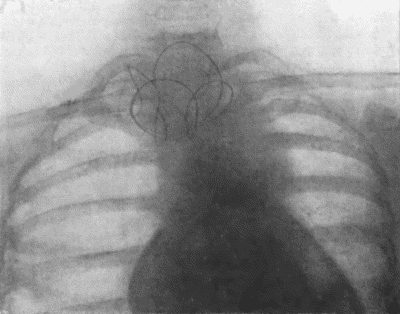

73.Radiogram of Innominate Aneurysm after Treatment by Moore-Corradi method 309

145.Radiogram of Myeloma of Humerus 492